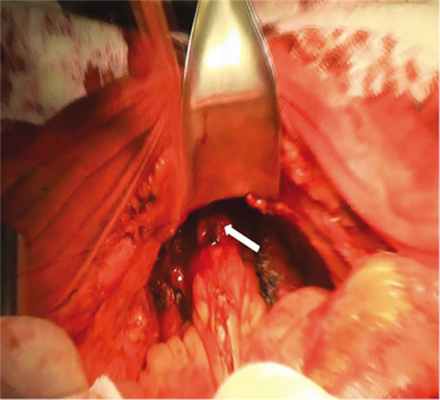

28.10.2019 выполнен второй этап — реконструктивно-восстановительный — в объеме тонкокишечной пластики влагалища (рис. 2 и 3, на цв.вклейке) сформированы ортотопический тонкокишечный мочевой пузырь, неоуретра.

Рис. 2. Интраоперационная фотография после выполненного адгезиолизиса, визуализирована полость малого таза, задняя стенка влагалища (указана стрелкой).

Рис. 3. Передняя стенка влагалища (указана стрелкой), сформированная из сегмента тонкой кишки (интраоперационная фотография).